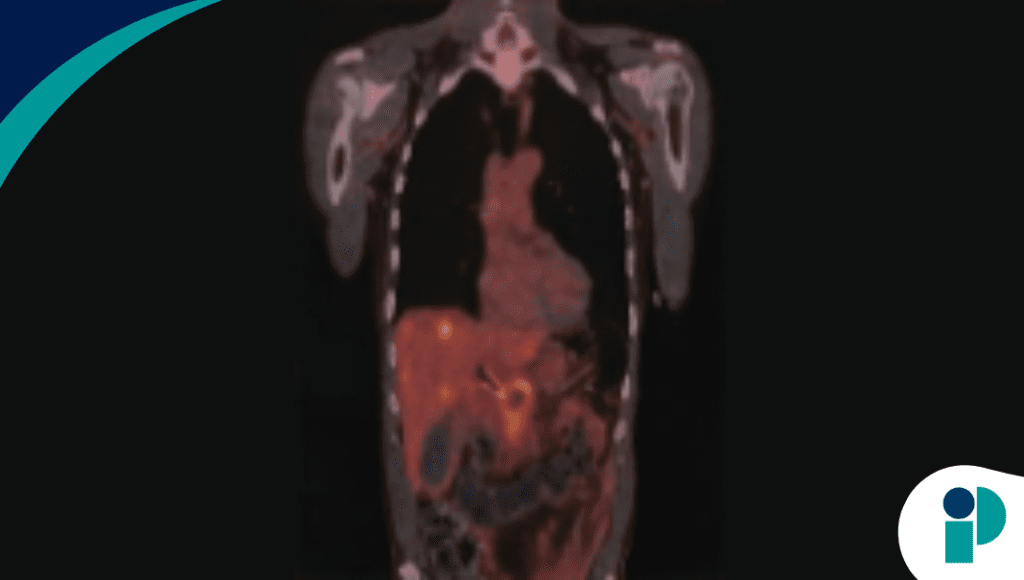

Se presenta el caso de un hombre de 65 años con antecedente de tabaquismo, quien consultó por dolor epigástrico, pérdida de peso y síntomas progresivos. Los estudios iniciales evidenciaron una masa pancreática de 2,7 × 3 cm con dilatación de la vía biliar y lesiones hepáticas sugestivas de metástasis. La biopsia confirmó adenocarcinoma pancreático.

Como parte del manejo, se realizó ERCP con colocación de un stent metálico autoexpandible para aliviar la obstrucción biliar. Posteriormente, el paciente reingresó con fiebre, escalofríos y deterioro clínico, estableciéndose el diagnóstico de colecistitis aguda secundaria a obstrucción del conducto cístico inducida por el stent.

A pesar de una mejoría inicial tras el manejo, el paciente presentó posteriormente dolor abdominal difuso y empeoramiento del estado general. Los estudios de imagen revelaron una colección intraabdominal compleja con contenido fecaloide y comunicación anómala entre la flexura hepática del colon y la cápsula hepática.

Estos hallazgos confirmaron la presencia de una fístula colecistocolónica, una complicación rara que se asocia generalmente a procesos inflamatorios crónicos de la vesícula biliar.